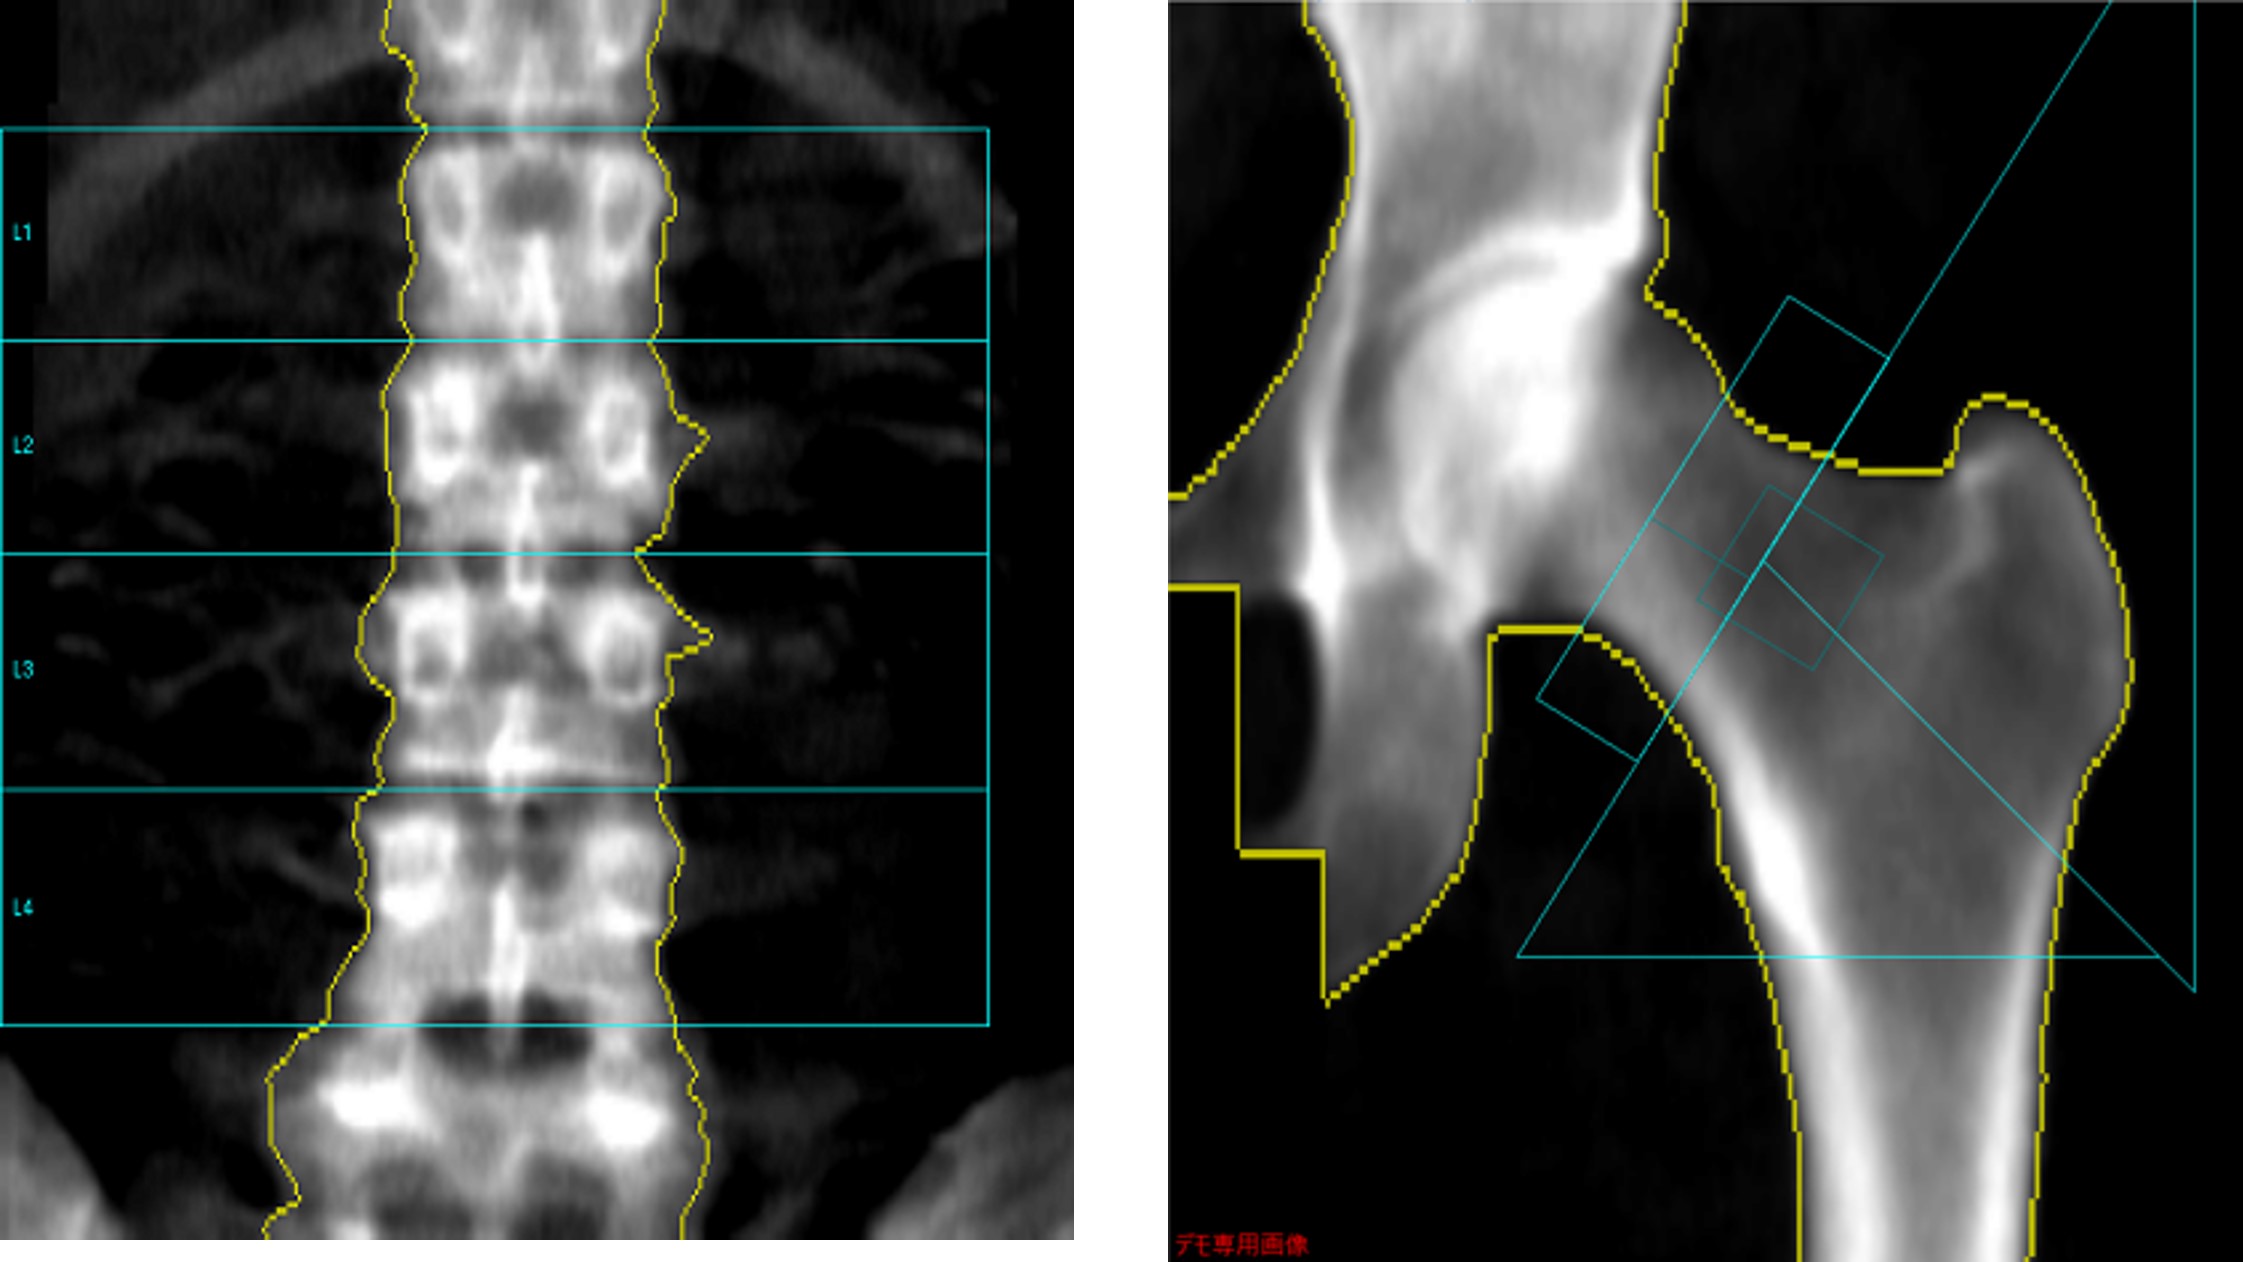

当院が使用しているGEヘルスケアの装置では、撮影範囲内に胆石等の極端に吸収値が異なる構造物が存在するとき、自動で「アーチファクト」として処理される。また、「骨領域」「軟部領域」だけでなく「ニュートラルポイント」という概念があり、骨量計算のうえで重要な機能だと感じている。これにより、腰椎横突起部など2次元画面上に軟部組織と骨が混在する部分や、大腿骨撮影範囲内の厚みが違う部分を計算から除外することができ、正確な検査の一助となっている。

Clinical Tips_yokohamashitobu04.jpg

軟部組織領域とニュートラル領域